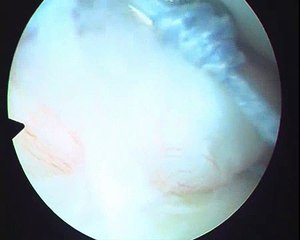

Indian dentist underwent shoulder stabilization surgery for recurrent shoulder dislocations. His recurrent dislocation was treated by Bankart repair by Dr.Venkatachalam in Chennai.